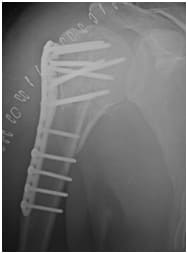

post operative X ray showing a (near!) Perfect repair!

You also require good therapy and guidance after your surgery to get the best results!!